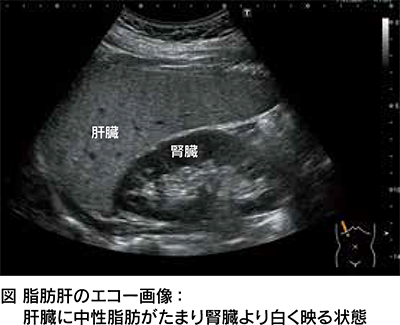

脂肪肝の初期は症状がなく、健康診断でのエコーや採血(肝機能や血糖値など)により見つかります。近年では、エコー検査で脂肪の量を数値化できる脂肪減衰法や、肝臓の硬さ(肝硬度)を調べて線維化の進行の程度を評価できる方法が普及しています(図)。また、採血で線維化を予測できる検査も多くあり、たとえば、血小板数の低下や、FIB-4index(フィブフォー・インデックス)という計算式を用いて、年齢・血小板数・AST・ALTなどの項目からも容易に推測できます。